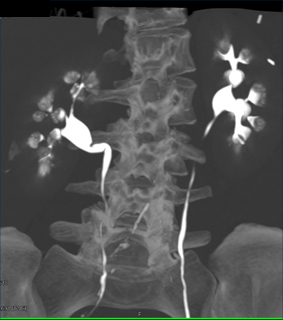

The best diagnosis in this CT Urogram is

transitional cell carcinoma

papillary necrosis

medullary sponge kidney

nephrocalcinosis